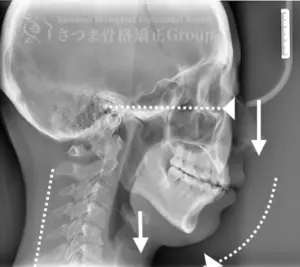

- 谷TMJ歯科クリニックでレントゲン撮影

- 撮影データを連係院へ提供

- TMJクリニックのドクターと連係院にて分析・施術計画の決定

施術の前後で撮影したレントゲン写真を比較することで、改善の度合いや変化を一目で確認できます。